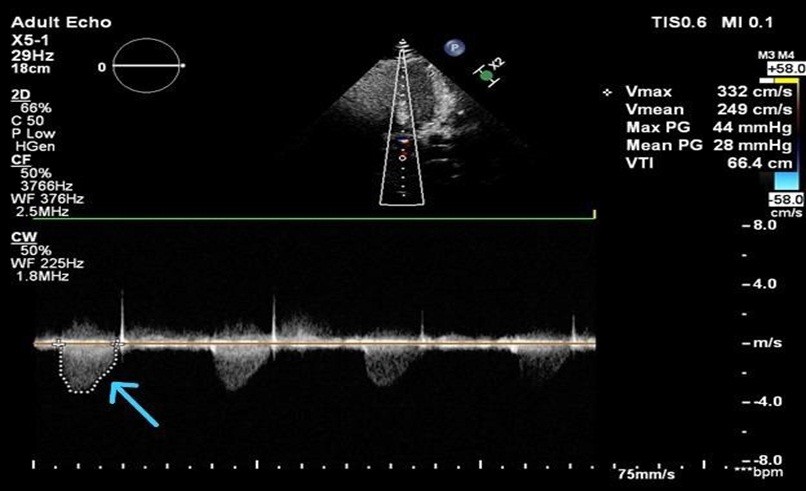

Cardiovascular imaging (echocardiography and cardiac magnetic resonce imaging, cMRI) confirmed SVAS. Transthoracic echocardiography revealed situs solitus, levocardia, supravalvular aortic gradient 44 mmHg, and mild concentric left ventricular hypertrophy (Fig. 3, 4).

Figure 4. Transthoracic echocardiography (apical view) with continuous-wave Doppler interrogation of the left ventricular outflow tract demonstrating high-velocity systolic flow across the supravalvular aortic region (arrow). Peak velocity (Vmax) is 3.32 m/s with a calculated peak pressure gradient of 44 mmHg and mean gradient of 28 mmHg, consistent with hemodynamically significant supravalvular aortic stenosis.